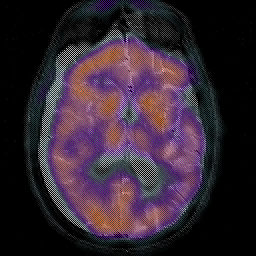

Subdural Hygroma,overlay -- Slice #26

[Home][Help][Clinical] Slice 26